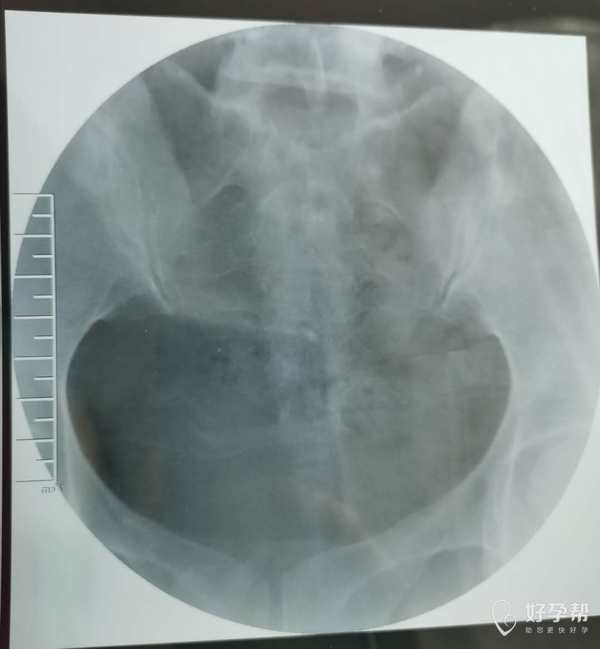

我这个是做了输卵管介入手术,请问输卵管是通了

你的片子提示双侧输卵管不通,未孕4年,合并腺肌症和腺肌瘤,建议你直接试管婴儿助孕。试管前不需要宫腹腔镜检查。